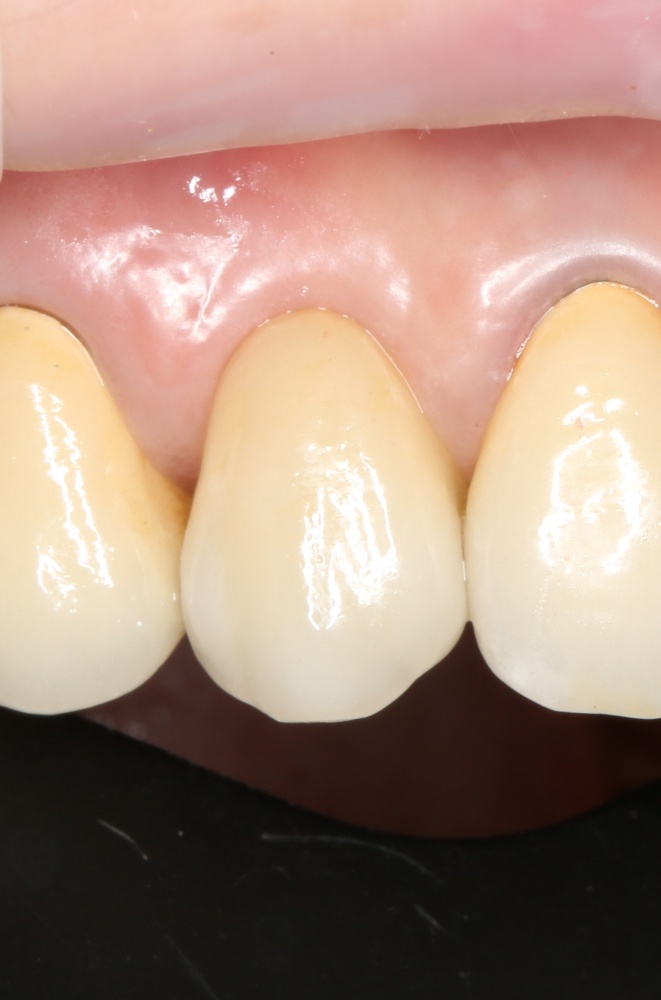

Рекомендации по установке имплантов. Для всех. Часть II.